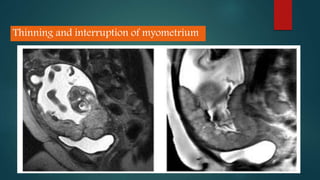

Ultrasound and MRI are used to diagnose placenta accreta, which occurs when the placenta invades the uterine wall due to prior uterine surgery or other risk factors. On ultrasound, signs include low placental implantation, lakes or indentations in the placenta, thinning of the myometrium, disruption of the uterine serosa, and abnormal blood flow on Doppler. MRI may show uterine bulging, a heterogeneous placenta, thinning and interruptions of the myometrium, obliteration of tissue planes, and dark bands within the placenta. These imaging findings help identify placenta accreta and guide management of delivery.